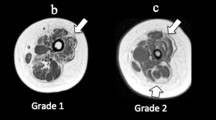

An elevated FF, as observed in our cohort, relates to chronic muscle degeneration and shows higher sensitivity compared to MRC testing and qualitative MRI in terms of capturing muscle degeneration in myopathies [26, 47]. Fatty infiltration is a sign of previous muscle damage with fatty replacement of irreversible damaged muscle fibers [48]. A high FF in muscle supports the hypothesis that long-term motor dysfunction and muscle fatigue in patients is caused by a myostructural deficit [2, 3, 14, 49]. FF values were only slightly elevated in ICU survivors compared to controls and still in a “normal” range. Whereas FF describes fatty infiltration very accurately and is easy to capture as percent fat per muscle, changes in the other qMRI modalities DTI and water T2 need to be closely interpreted with the expected or known disease pathology.

Whereas CIM is transient and only reflects myostructural damage due to direct muscle injury in the acute phase of ICU therapy, CIP in contrast is long-lasting due to nerve injury and serves as the major cause of functional debilitation [50]. Neurogenic myofiber atrophy due to axonal loss is usually irreversible and has already been described in muscle biopsies of CIP patients [51].

Our electrophysiologic studies show predominantly axonal nerve damage in calf nerves of patients and clinical data underline that CIP usually affects distal limbs [51]. Since we confirmed a polyneuropathy in our patient cohort, consistent with CIP, our observed differences of qMRI parameters reflect neurogenic muscle damage. The observed higher FA in patient muscles shows a higher proportion of axial compared to radial diffusion. In neurogenic myofiber atrophy, myofibers do not lose their structural integrity initially but get atrophic. This atrophy leads to myofiber diameter reduction and consequently to an increase in FA [29, 52]. MD usually reflects the degree of overall diffusion as it equally integrates the eigenvalues λ1- λ3 as a simple mean value (MD = \(\frac{\sum (\lambda 1, \lambda 2,\lambda 3)}{3}\)) and is elevated in active muscle degeneration and inflammation whereas a reduction of MD is seen in muscle atrophy without an active degeneration. The relation of MD and FA values is usually fixed [29]. Thus a solely myofiber atrophy would lead to an increase in FA and a decrease in MD whereas an inflammatory edema would counterwise lead to a decrease in FA and an increase in MD (as well as RD, and λ2–3) [29]. Interestingly, in our patients, FA and MD are both significantly higher than in controls mostly pronounced in the calf muscles. A combination of a high FA and a high MD supports a parallel chronic myofiber atrophy and active myofiber degeneration.

Thus, we hypothesize that our observed combination of unanimous elevated MD, water T2, FA and FF reflect parallel active muscle degeneration and myofiber atrophy in chronic damaged muscle tissue due to ICUAW. Although FF is significantly increased between the two groups, the absolute value is still comparably low, so that an influence of the FF on the DTI parameters can be ruled out [56, 57]. This hypothesis is also underlined by a separate analysis of thigh and calf muscle qMRI values and by our clinical outcomes.

In thighs, compared to calves, chronic muscle degeneration is predominantly observed as MD is only mildly elevated compared to calves and water T2 is not elevated. In contrast, MD and water T2 are highly elevated in calves and reflect active muscle degeneration. Our data support that chronic axonal nerve damage in calves due to CIP leads to an ongoing myofiber damage and breakdown.